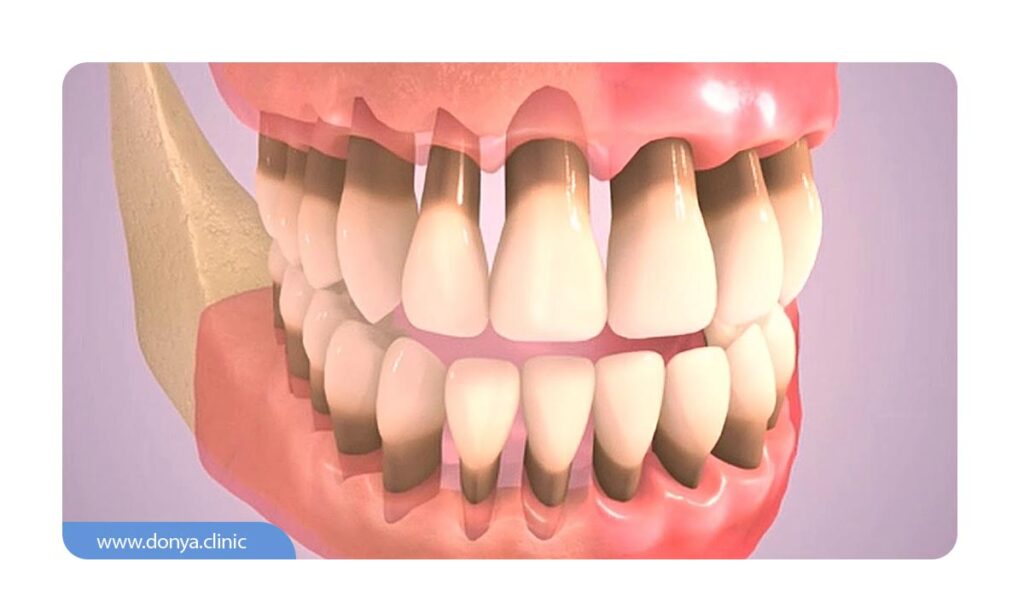

تحلیل لثه یا (Gum recession) نوع رایجی از مشکلات دندانپزشکی است که در آن، حاشیه بافت لثه (که دندان ها را احاطه کرده) از بین رفته یا نازک می شود. اصطلاحاً به این مشکل عقب نشینی لثه نیز گفته می شود. زمانی که لثه تحلیل می رود، ریشه دندان ها نمایان می شود و مشکلات زیادی برای افراد ایجاد می شود.

تحلیل لثه، که به آن عقب نشینی لثه نیز گفته می شود، وضعیتی است که در آن لثه ها شروع به کوچک شدن و عقب نشینی از دندان ها می کنند. این می تواند منجر به بیرون زدگی ریشه دندان ها شود و در صورت عدم درمان، به بیماری های جدی دهان و دندان منجر گردد. در اینجا برخی از علائم و نشانه های رایج آن آورده شده است:

- منقبض شدن مشهود لثه ها که در آن لثه ها به نظر کوچک تر و دندان ها بلندتر به نظر می رسند.

- مشخص شدن ریشه های دندان که توسط لثه پوشیده می شوند.